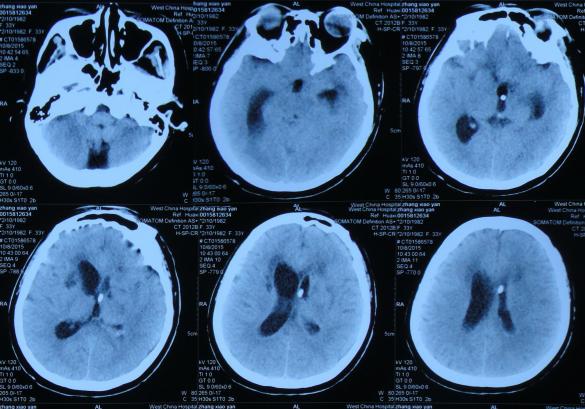

2016年6月3日住入李小勇脑脊液中心,入院时:卧床,反应慢,表情淡漠,言语迟钝(问答无反应),吞咽困难,只能鼻饲流食,头部有多处手术疤痕,右下肢自主活动差,但刺激后能动(图-25);入院第2天即2016年6月5日,头部CT示脑积水,脑室粘连,脑萎缩(图-26)。

图-26:2016年6月5日头部CT入院时

入院后4天即2016年6月7日,进行了脑室腹腔分流管取出术+脑室腹腔分流泵取出术+脑室外引流术+脑室腹壁外引流术+透明隔造瘘术,术后当天查头部CT示脑室引流术后(图-27)。

图-27:2016年6月7日术后头部CT

入院治疗2个月时间内,虽脑室缩小,但仍有结核性脑脓肿(图-28、图-29),且病情持续加重致昏睡,不能遵嘱活动,不能言语。

图-28:2016年6月12日

图-29:2016年6月22日